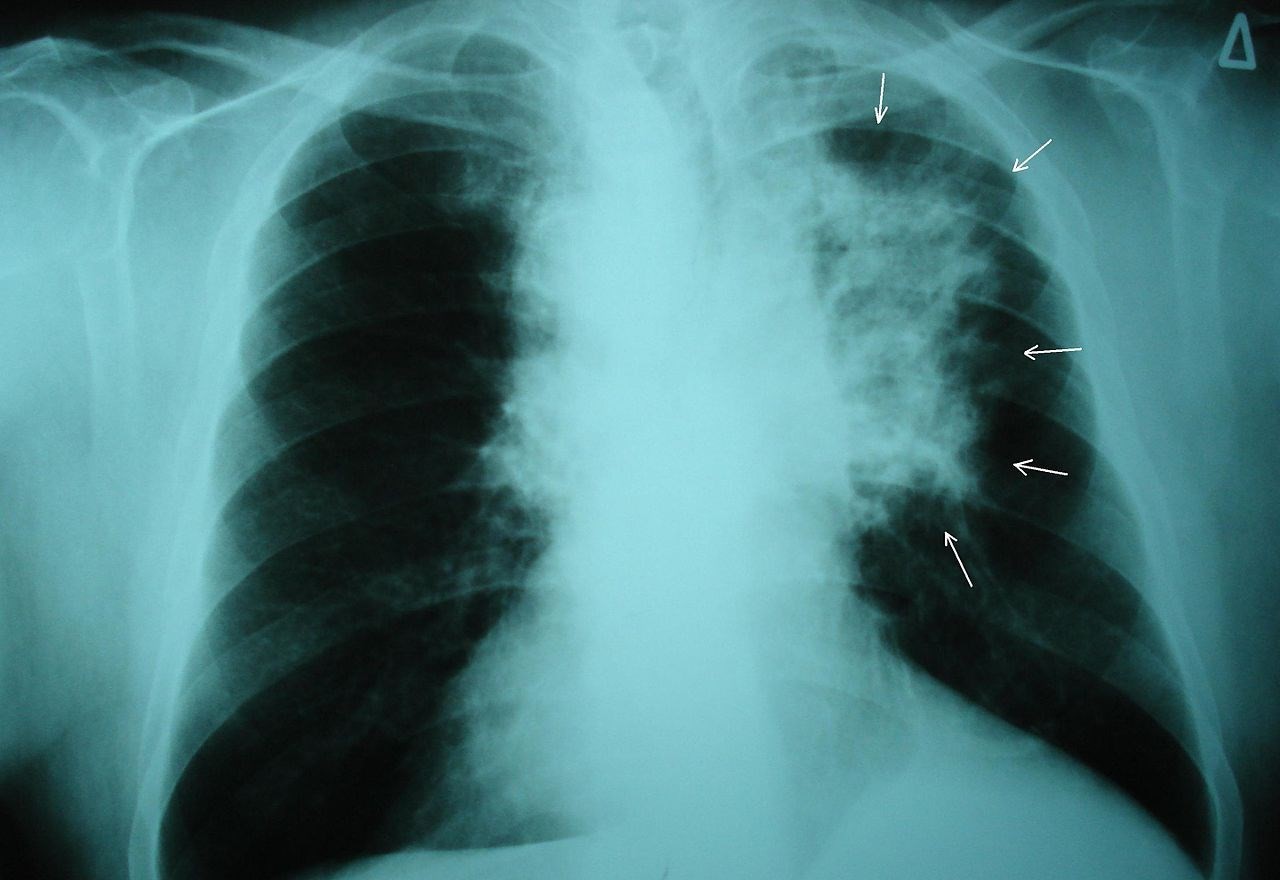

¿Qué pasaría si los modelos de aprendizaje profundo pudieran detectar el cáncer en las primeras etapas del mismo con mayor precisión que un radiólogo veterano? La tasa de supervivencia de los pacientes de cáncer en caso de detección temprana suele ser alta (en […]